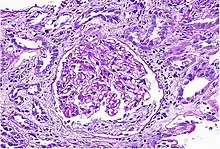

| Acute interstitial nephritis on light microscopy | |

While non-invasive patient evaluation (physical examination, blood and urine testing, imaging studies) can be suggestive, the only way to definitively diagnosis interstitial nephritis is with a tissue diagnosis obtained by kidney biopsy. Pathologic examination will reveal the presence of interstitial edema and inflammatory infiltration with various white blood cells, including neutrophils, eosinophils, and lymphocytes. Generally, blood vessels and glomeruli are not affected. Electron microscopy shows mitochondrial damage in the tubular epithelial cells, vacuoles in the cytoplasm, and enlarged endoplasmic reticulum.[23]